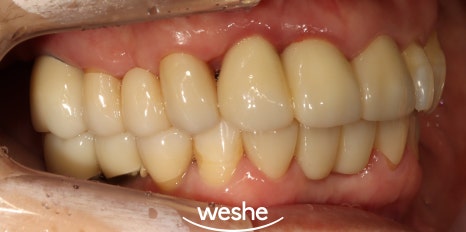

송정역 치과 치료 기간 : 2023.05.12~2024.02.14